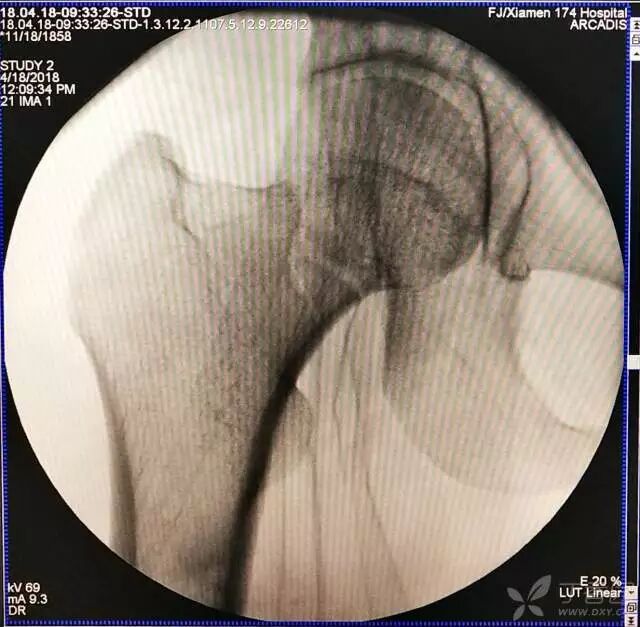

1. 对于难复性股骨颈骨折,术前应做好切开复位的准备,该患者复位三次都不太满意。

牵引床怎么用视频详解:如何不使用牵引床做好一台股骨颈骨折?_https://www.jmylbn.com_新闻资讯_第9张

2. 倒数第二次的复位仍是欠缺一点